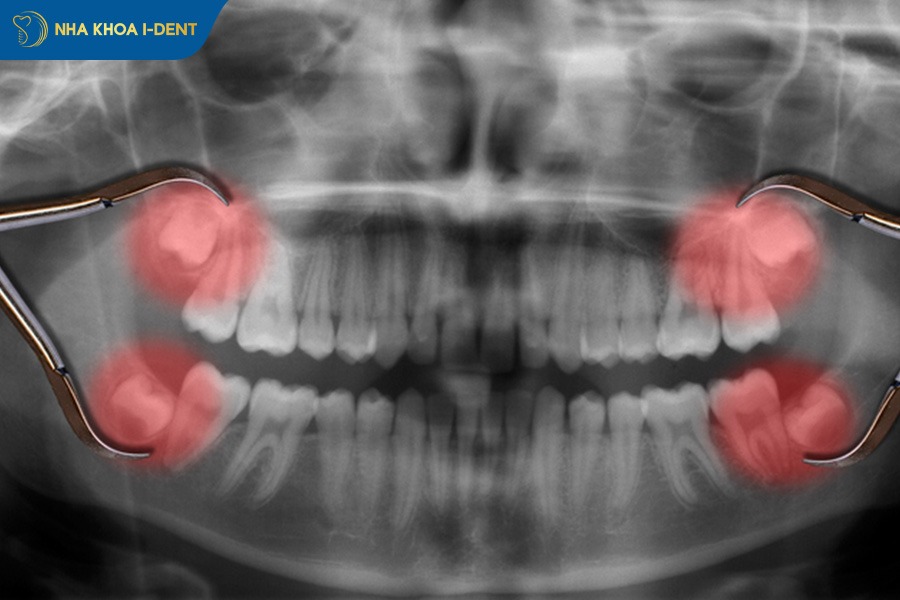

2.5. Răng mọc ngầm

Răng mọc ngầm là tình trạng răng không mọc đúng vị trí trên cung hàm mà nằm ẩn hoàn toàn hoặc một phần trong nướu, xương hàm và một ngày nào đó sẽ tách nướu trồi lên. Tình trạng này thường gặp ở răng nanh và răng khôn.

Khi răng mọc ngầm thì các răng bên cạnh có thể bị xô lệch, chen chúc làm mất cân đối cung hàm và gây khó khăn trong việc vệ sinh. Răng mọc ngầm cũng có thể tạo nang quanh răng gây đau âm ỉ, viêm nhiễm hoặc đẩy các răng còn lại ra khỏi vị trí ban đầu.

Trong chỉnh nha, việc xử lý răng mọc ngầm được thực hiện bằng cách mở đường bộc lộ răng ngầm và gắn khí cụ để kéo răng lên đúng vị trí trên cung hàm. Đây là kỹ thuật đòi hỏi bác sĩ có chuyên môn cao và được thực hiện theo từng giai đoạn để đảm bảo răng dịch chuyển an toàn. Trong một số trường hợp, bác sĩ sẽ khuyên bệnh nhân nhổ bỏ thay vì niềng.

Xử lý răng mọc ngầm để kéo răng lên đúng vị trí trên cung hàm.